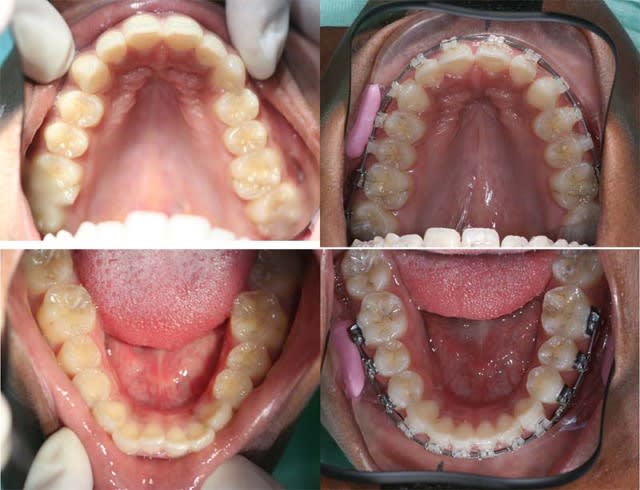

Ce cas est assez banal, il montre les possibilités de reformage de l’arcade Md. avec des systèmes à faible friction

voici une comparaison de l’évolution des formes d’arcades sup et inf

11 ans, 18 ans, 19 ans

voyez ce qu’on peut obtenir en 1 an

Je ne sais pas si vous êtes d’accord, mais la forme d’arcade inférieure à 19 ans ressemble à celle à 11 ans

à l’arcade inférieure, je n’aurai donc fait que récupérer la forme originelle